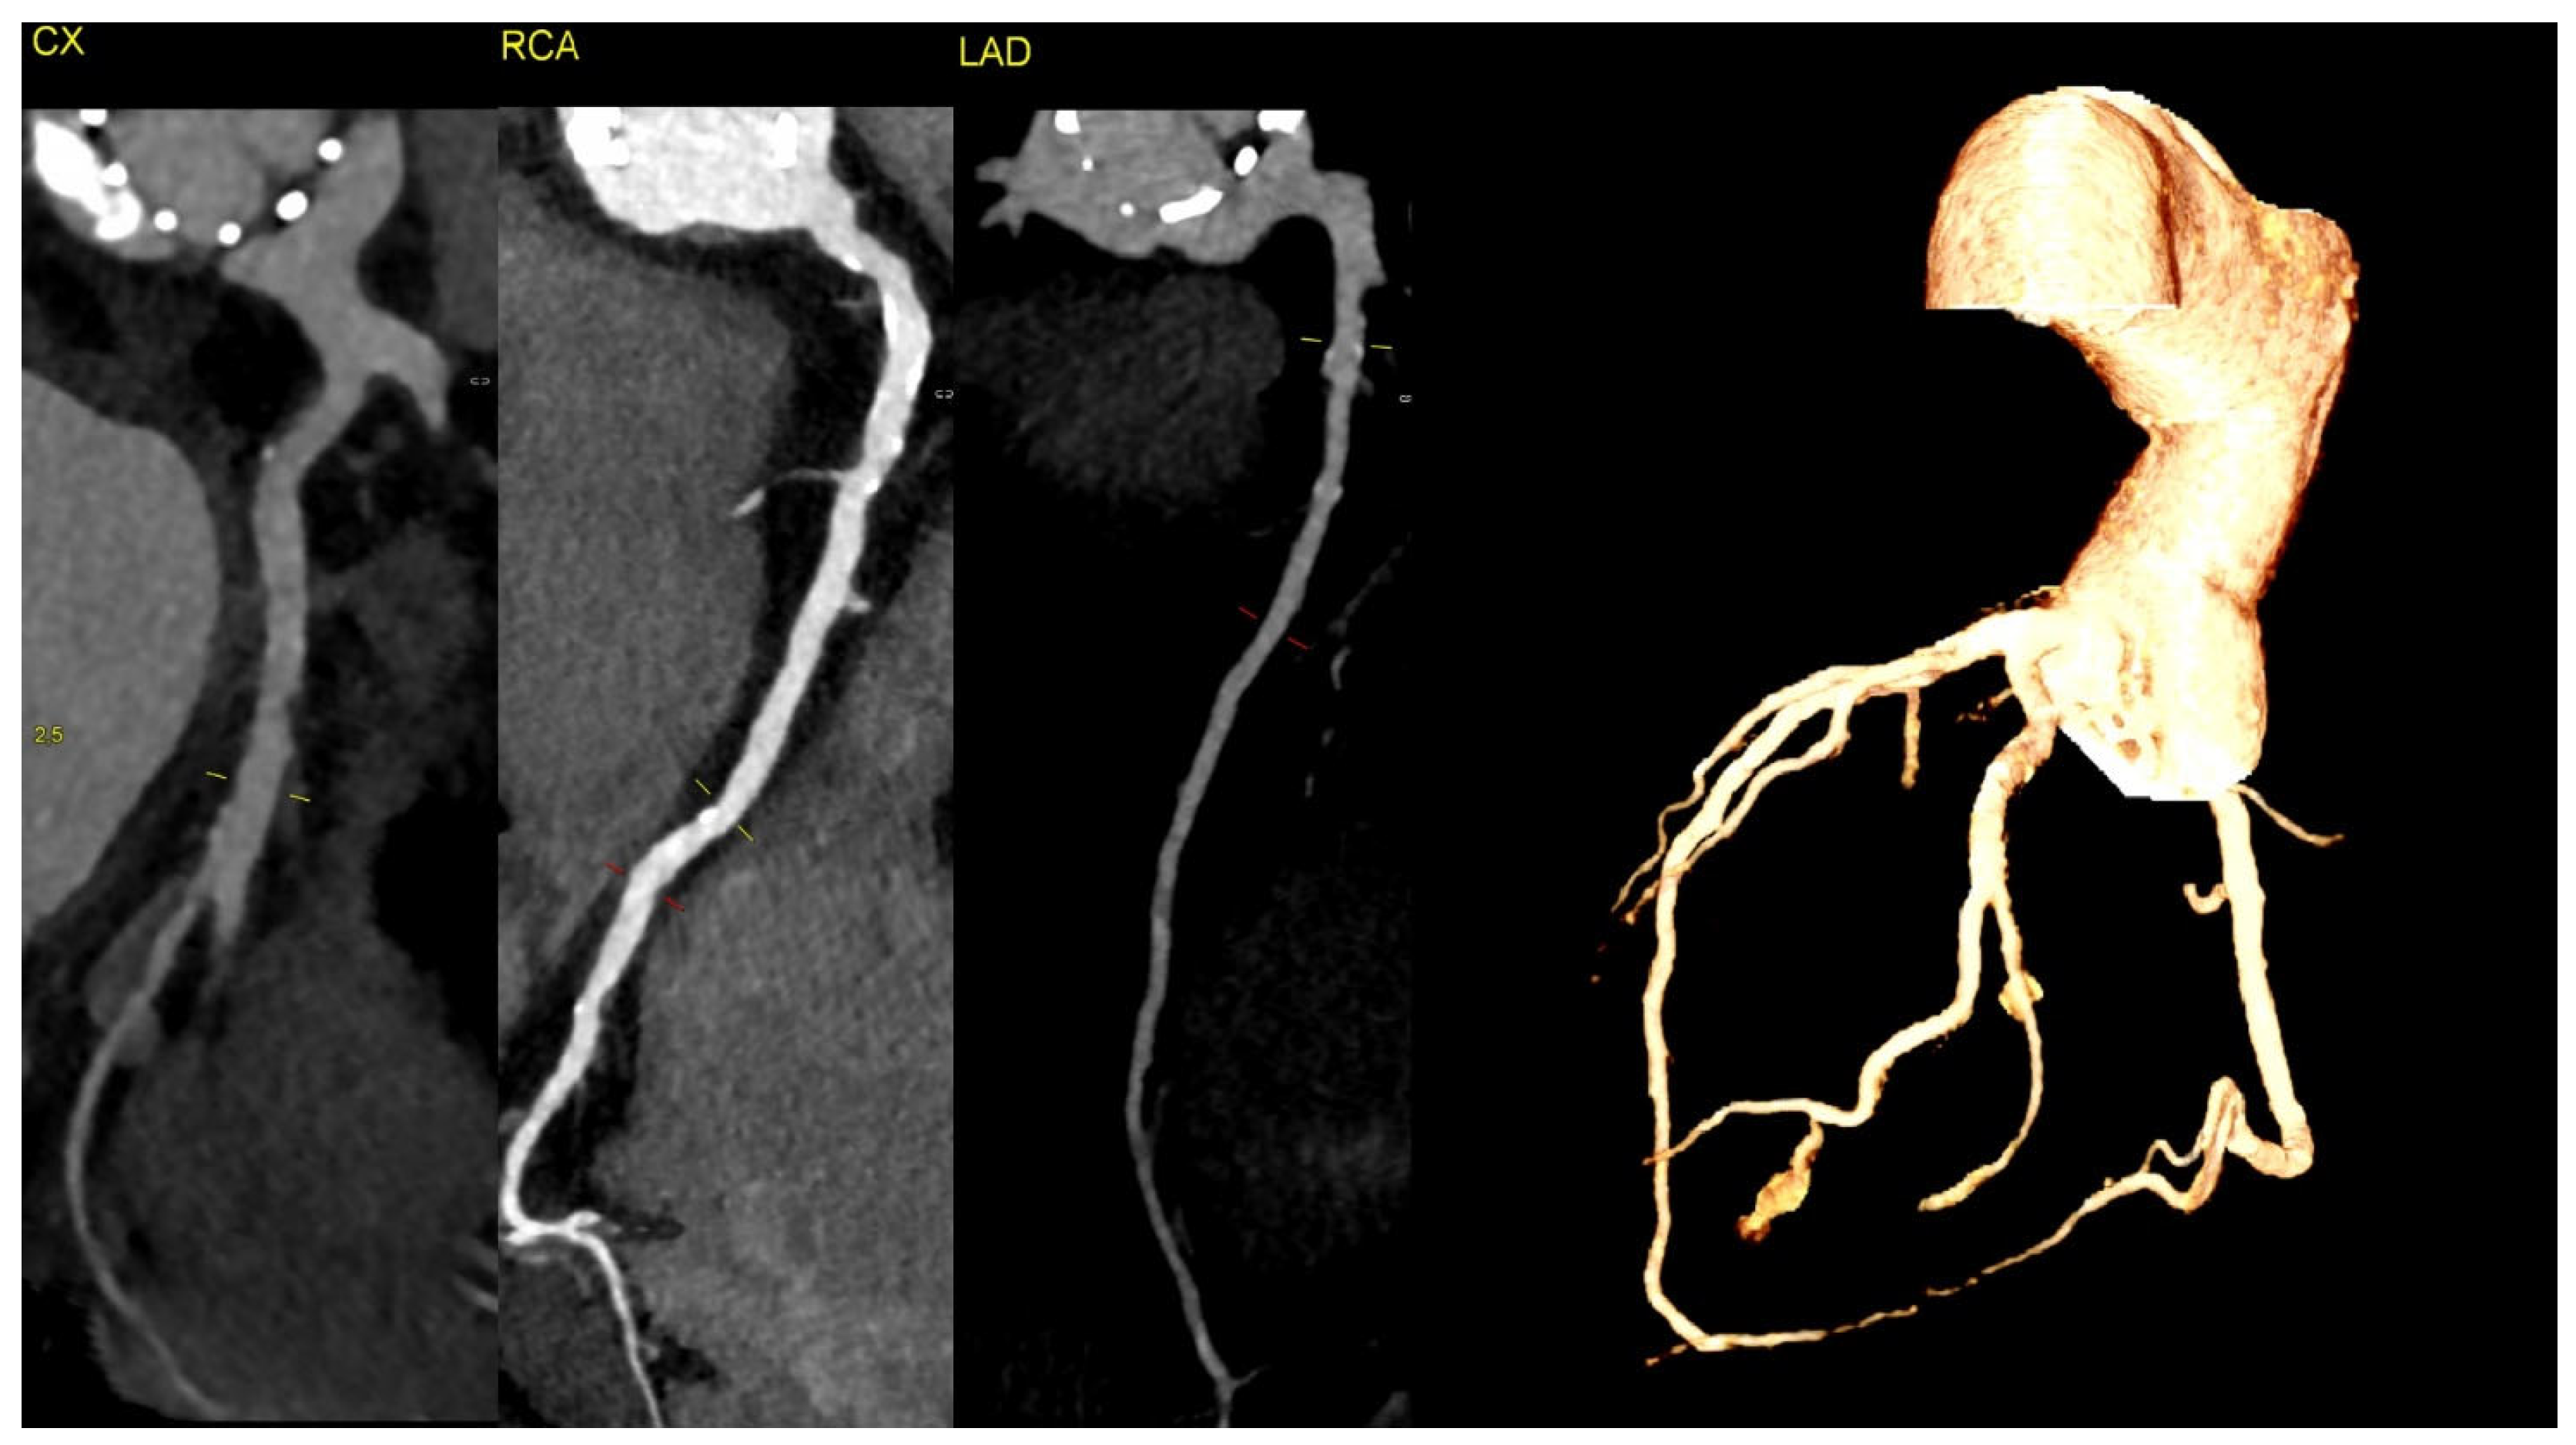

The CT discluded significant coronary artery stenosis (Cx—circumflex artery, RCA—right coronary artery, LAD—left anterior descending artery). The myocardial infarction was treated conservatively with anticoagulation due to the presence of aortic graft and valve thrombosis, and it led to the resolution of the chest pain. The clinically insignificant lesions in the coronary arteries on CT were suggestive of the fact that NSTEMI could be caused by the occlusion of the ostium of the arteries by the aortic valve thrombus.